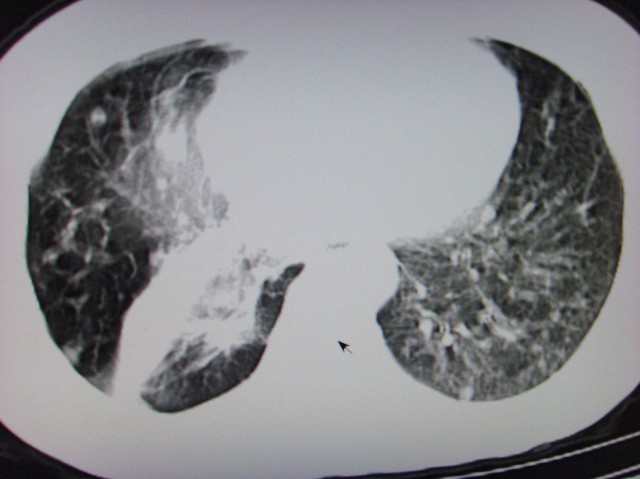

右下中心型肺癌伴双肺转移、纵隔淋巴结转移,癌性淋巴管炎可能性大

典型--右下中心型肺癌伴双肺转移、纵隔淋巴结转移,癌性淋巴管炎可能性大

中心型肺癌伴双肺转移及纵隔淋巴结转移,癌性淋巴管炎

首先考虑中央型肺癌伴阻塞性肺炎双肺、淋巴结转移,可以正规抗炎治疗一周后复查